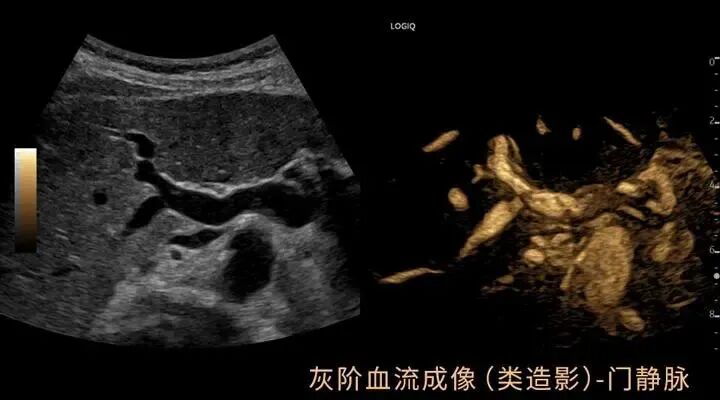

GE LOGIQ-Fortis Plus在甲状腺、乳腺、双下肢、颈部血管等检查项目方面有明显优势,对微血流的显示和弹性成像技术有全新的视野,图像更清晰细腻,血流显示立体逼真,能够实现二维条件下血流的“立体浮雕式”呈现,减少彩色血流闪烁,增强细微血管的可视化成像效果有利于临近交叉血管的边界识别。